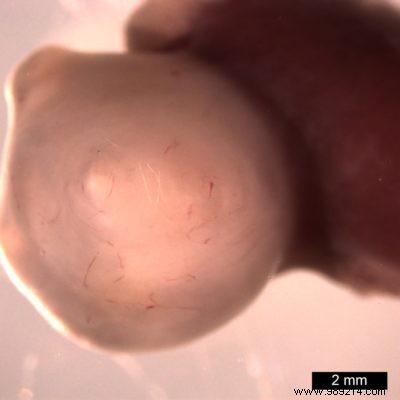

After roughly 30 days in culture, the organoids were transplanted into mice. Benefiting from blood supply and ample space, they expanded over 1,000 times larger than in vitro.

Remarkably, these mini-organs developed features like Brunner's glands, which secrete protective alkaline mucus to shield the upper intestine from stomach acid—a trait impossible in standard cultures.